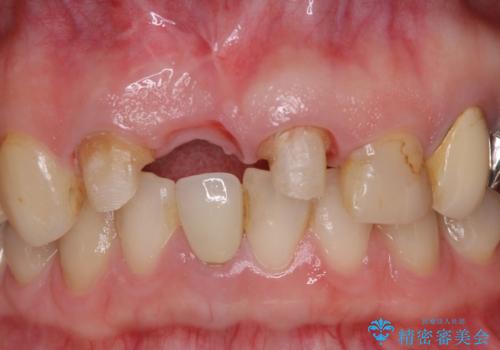

鼻の下を押すと痛い 抜歯を避けてきた歯を抜歯して自然な口元に

- 以前から前歯の根が折れていると言われていたものの放置しており、いよいよ痛みが気になってきたとのことで来院された患者様です。

検査の結果、右前歯の歯根が縦に破折していることが分かりました。

破折している歯は抜歯をし、歯肉が窪んでしまうので、傷口の治りを待って、歯肉移植を行うこととしました。

歯肉移植終了後、オールセラミックブリッジにて補綴することとしました。